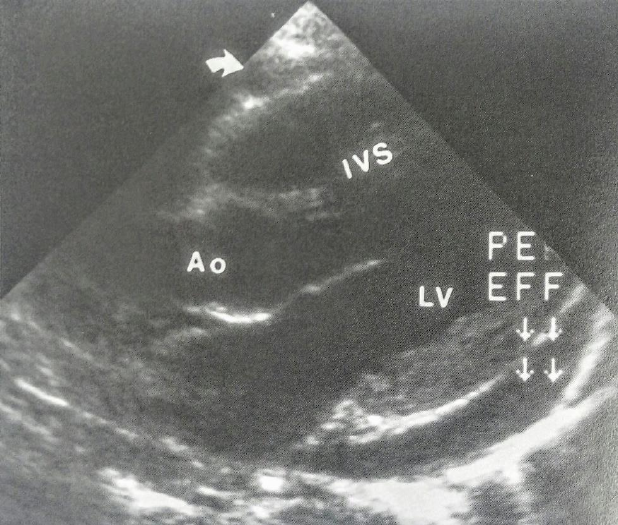

Derrame Pericárdico.

Ecocardiograma longitudinal

através do septo

interventricular (IVS), da raiz

aórtica (Ao) e do VE (LV)

demonstrando derrame

pericárdico (PE EFF).

Também há um derrame

anterior menor (seta);